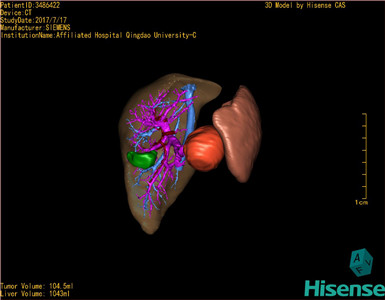

术前三维重建及手术方案设计:

将0.625mm双源薄层CT资料的静脉期和动脉期Dicom格式文件导入海信CAS系统。

通过调节窗宽窗位调整CT序号,对肿瘤,肝实质,胆囊,下腔静脉,肿瘤,肝动脉、门静脉及肝静脉等进行三维重建;系统自动计算肿瘤体积和肝脏体积。

模拟手术操作,自动计算切除肿瘤体积。肝脏体积为1096ml,胰腺肿瘤体积为115.5ml,通过比对12-13岁正常肝脏体积为1116.86±158.78 ml,通过术前模拟手术,精准判断切除后肝脏体积无明显变化,避免肝衰竭发生。

术前三维重建:

重建图片